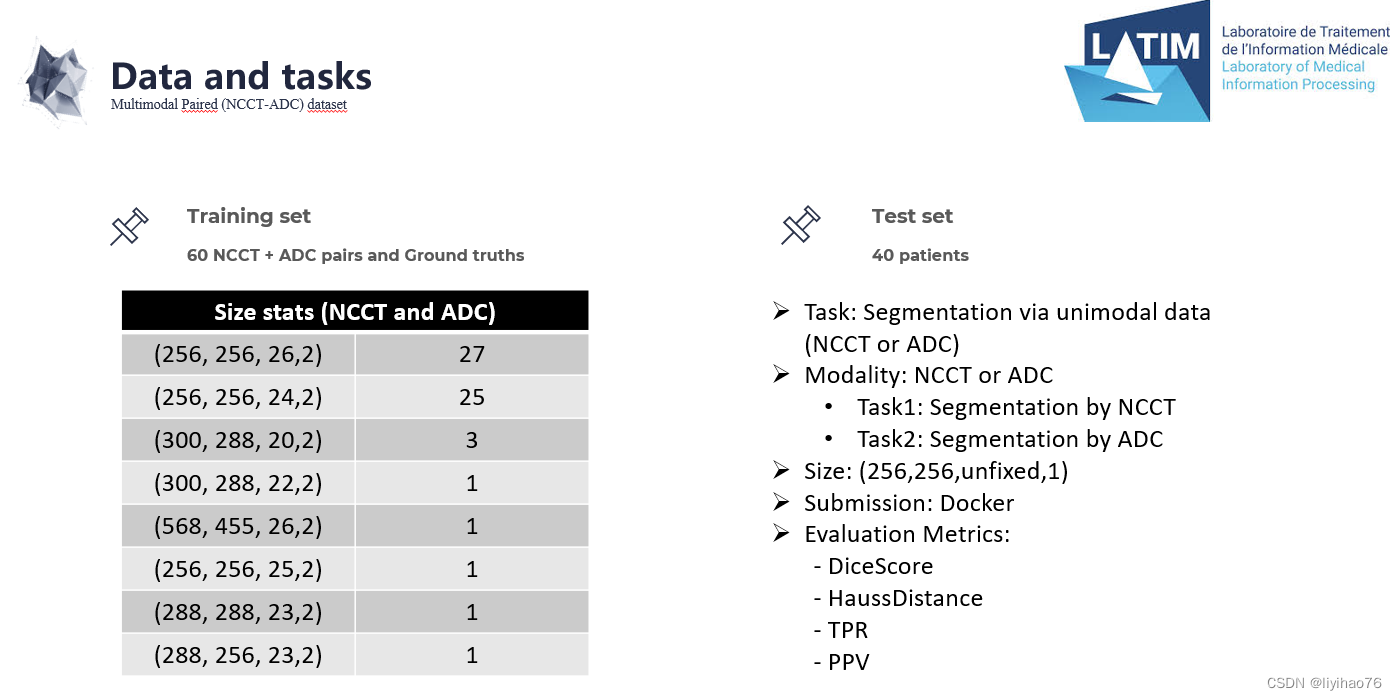

CT (NCCT) 主要允许对中风和其他病理进行分类。 然而,此类序列对缺血的对比度差、敏感性和特异性低,并且病变的低衰减具有时间依赖性。因此,临床方案包括扩散加权 MRI 序列,例如 ADC(表观扩散系数),以正确描述和量化中风病变,除其他外,允许正确显示缺血半影和缺血核心。APIS 挑战赛提供配对 (CT-ADC) 数据集。 有 60 个成对的 (CT-ADC) 数据集以及来自专业放射科医师的相关描述以供训练。 最后将使用40个数据集作为测试集进行验证

1.比赛任务及结果